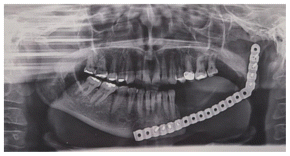

Due to the size of the lesion a mandibular titanium rod was placed to preserve the the lower portion of the mandible and part of the ascending ramus and condyle of the mandible (Figures 6,7,8) In the panoramic rx, the placement of the titanium rod can be seen to fix the ascending ramus with the condyle and the right side of the mandible with the resection to the level of the left lower canine (Figure 9).